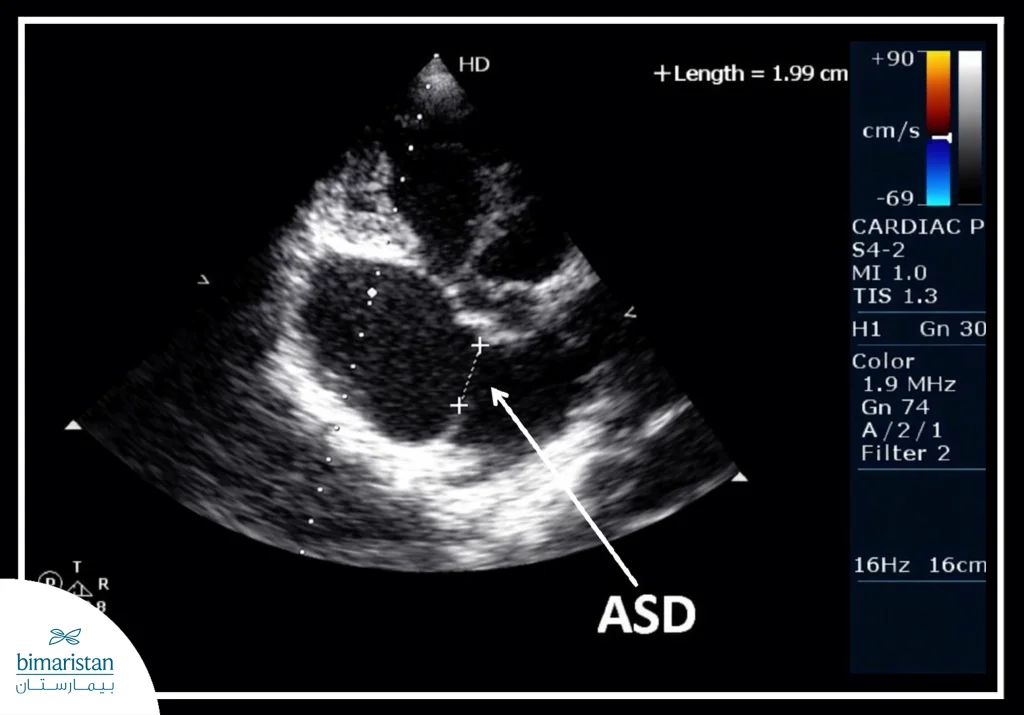

- تخطيط صدى القلب (الإيكو): يُعد الفحص الأساسي لتشخيص عيب الحاجز الأذيني، حيث يُظهر حجرات القلب وصماماته، ويقيّم حركة الدم داخل القلب ووجود التحويل غير الطبيعي للدم بين الأذينين.

- تخطيط صدى القلب عبر جدار الصدر(TTE): يُستخدم لتقييم تأثير العيب على القلب والرئتين، بما في ذلك التحويل من الأذين الأيسر إلى الأيمن.

- تخطيط صدى القلب عبر المريء (TEE): يساعد في تحديد حجم الفتحة وشكلها وموقعها بدقة أكبر، إضافة إلى تقييم الصمامات القلبية.